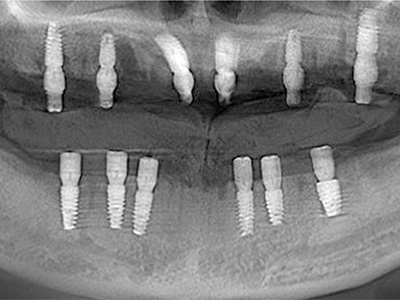

病例应用